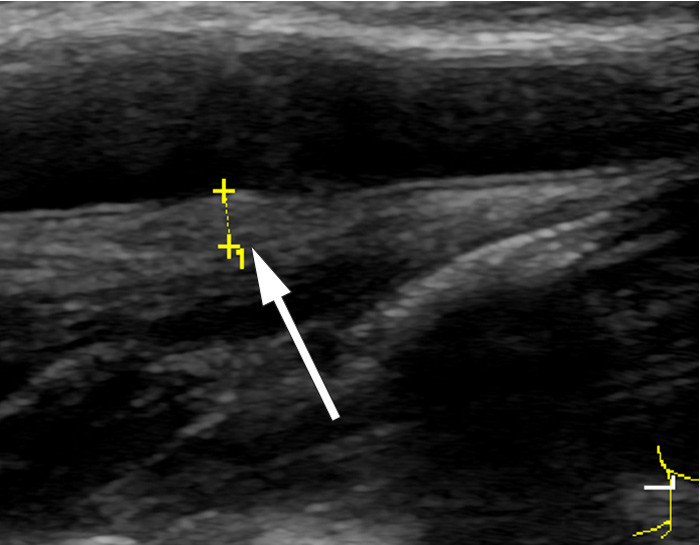

Ved klinisk undersøkelse fant man palpasjonsømhet under høyre bifurkatur. Det var ingen nevrologiske utfall. CT angio av halskar viste intet sikkert patologisk. Derfor ble det gjort ny ultralyd av halskarene, og man fant normalt kaliber av aktuelle carotisbifurkatur. På stillbilder var det vanskelig å se noe galt, men med løpende avbildning så man en isodens fortykkelse i åreveggen som ble oppfattet som en disseksjon. Forandringen var forsvunnet ved ultralydkontroll fire måneder senere, noe som bekreftet diagnosen. MR angio tatt seks uker etter symptomstart viste normale halskar.

Hos denne pasienten var vegghematomet isodenst og vanskelig å se på stillbilder, særlig ved den siste ultralydundersøkelsen (bildet til høyre). Ved den initiale undersøkelsen fremsto det noe tydeligere (bildet til venstre). På videoene kan man se disseksjonen som en veggfortykkelse som beveger seg sammen med karet og ikke med det underliggende vevet.